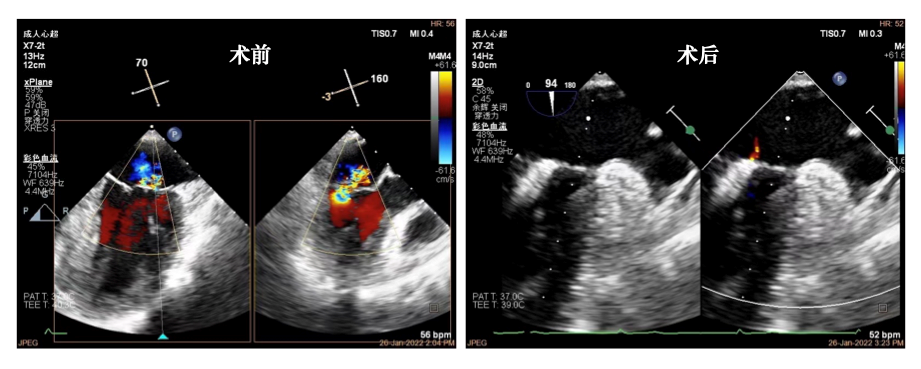

在充分做好术前综合评估的基础上,麻醉科专家为患者实施了全身麻醉,汪芳教授团队采用突破性治疗技术,经穿刺右侧股静脉,送入血管鞘及房间隔穿刺针,在食道超声引导下,穿刺房间隔,沿超硬导丝送入MitraClip引导鞘,再送入MitraClip系统,然后经数次微调,在二尖瓣P1-P2脱垂反流处植入MitraClip XTR一枚。整个手术过程非常顺利,术后即刻经食道超声心动图等评估,患者二尖瓣返流明显减少至消失,跨瓣平均压差1mmHg,肺静脉返流消失,其他各项生理指标正常,手术取得圆满成功。

手术前后食道超声心动图比较,可见二尖瓣反流明显减少至消失

超声心动图作为心血管内科的重要辅助检查,在心脏结构的细微清晰辨认指引中发挥了极大的作用,既是心血管内科新技术发展的积极成果,也是多项技术融合的最佳体现之一。该例微创治疗,正是由于全程采用食道超声引导房间隔穿刺和定位技术,患者无需进行传统开胸手术和体外循环,还有效避免了放射线辐射带来的损伤,在术后1天即可下地活动。